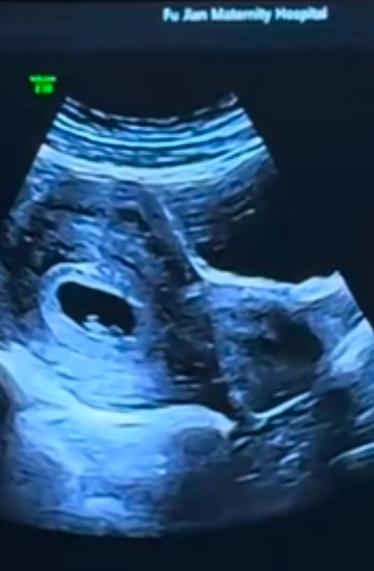

遭心,气哭了,女子二婚,未婚先孕,未怀孕之前,婆家说下彩礼18万,买三金,结果先怀孕了,婆家出而反而,说愿意结婚就结,不愿意结婚自己看着办,反正手里现在没钱,女子一气之下去医院引产了。网友:难道二婚的女人怀孕就一文不值了吗? 那天一早,小赵原本是要去医院做产检的。 她前一晚还特意把所有检查单整理好,装进文件袋里。医生说胎心有点弱,让她这次一定要按时去复查。 她心里既紧张又期待,肚子里的孩子已经快三个月了,虽然还没成形,却已经在她的生活里占据了全部位置。 就在她换鞋准备出门时,男友忽然开口了。 语气很随意,像是在说一件早就商量好的小事。 “我妈说了,既然你已经怀孕了,那咱们就先把婚结了吧,订婚就不订了。” 小赵愣了一下,手里的包停在半空。 “……不订婚?” “嗯,省事。” 她转过头,看着男友的脸,那张曾经在她最脆弱的时候说过“我一定负责”的脸,此刻却没有半点犹豫。 她忍不住问了一句:“那彩礼呢?” 这句话,她问得很轻,却像是在给自己最后一点心理准备。 男友叹了口气,说得理所当然:“我妈说,家里的钱都给咱们买房子、装修房子了,真没钱了。” 他顿了顿,又补了一句:“我妈也不容易。” 小赵的心一点点往下沉。 “那之前说好的彩礼和彩礼数额呢?” “那不是还没订吗?现在情况不一样了。” 她站在原地,觉得脚底像踩空了一样。 男友见她没说话,又继续劝:“你看你现在也怀孕了,先把孩子生下来再说其他的。反正咱们都要结婚了,形式那些东西,也没那么重要。” 形式? 她忽然想起,恋爱初期,对方母亲拍着胸脯说过的话—— “我们家不差你那点钱,彩礼是态度。” “该给的一分不会少。” 可现在,一句“先把孩子生下来”,就把一切都抹掉了。 她低头看了看自己的肚子,那里还很平坦,却仿佛压着一座山。 去医院的路上,她一句话都没说。 男友刷着手机,偶尔抬头问一句:“你咋不说话?” 她张了张嘴,却不知道从哪里说起。 到了医院,排队、挂号、等候,她整个人像被抽空了一样。医生一边看检查单,一边皱眉:“最近是不是情绪波动比较大?” 她点了点头。 “孕早期情绪对胎儿影响很大,要尽量放松。” 这句话像一把刀,扎得她眼眶发热。 从医院出来,她终于忍不住了。 “我不是非要你们家的钱,”她声音发抖,“可彩礼是对我的尊重,是给我父母的交代。” 男友不耐烦地皱眉:“你怎么这么想不开?都怀孕了,还纠结这些干嘛?” “我纠结的不是钱,是你们的态度。” 他沉默了几秒,说:“你要是真为孩子着想,就别闹了。” “别闹”这两个字,让她彻底失语。 那天晚上,小赵回到家,坐在床上发呆。她翻看手机里以前的聊天记录,一句句看过去—— “我妈说你放心。” “彩礼一定给足。” “你跟了我,不会吃亏。” 现在再看,每一句都像笑话。 第二天,她鼓起勇气,主动约男友母亲谈。 她坐在未来婆婆家的沙发上,双手紧紧攥着衣角,小心翼翼地开口:“阿姨,彩礼的事……之前不是说好了吗?” 婆婆连茶都没倒,直接回了一句:“现在情况变了。” “钱都投在房子上了,你要是真想过日子,就别太计较这些虚的。” 小赵声音发哑:“可我父母那边……” “你都怀孕了,还好意思跟家里要彩礼?”婆婆打断她,“说句不好听的,现在你不嫁,还能嫁给谁?” 那一刻,小赵的脑袋“嗡”地一声。 她忽然意识到,从怀孕那一刻起,她在这家人眼里,就从“被选择的人”,变成了“已经被拿捏的人”。 回家的路上,她哭到喘不上气。 不是为钱,是为自己一步步退让到没有退路。 几天后,她再次提出彩礼问题,男友终于不耐烦了。 “你要么结婚,要么别结。” “孩子你自己看着办。” 这句话,像一根最后的稻草。 那天晚上,小赵一夜没睡。 天亮时,她一个人去了医院。 护士问:“家属呢?” 她低声说:“没有。” 签字时,她的手抖得几乎握不住笔。 手术室的灯亮起之前,她闭上眼睛,眼泪顺着眼角滑落。 她失去的,不只是一个孩子,还有对“先结婚再说”的全部幻想。 后来,她走出来了。 可每当想起那句——“先把孩子生下来,再说其他的。” 她就忍不住想问一句:如果连尊重都要等到以后,那这个“以后”,真的还值得吗?